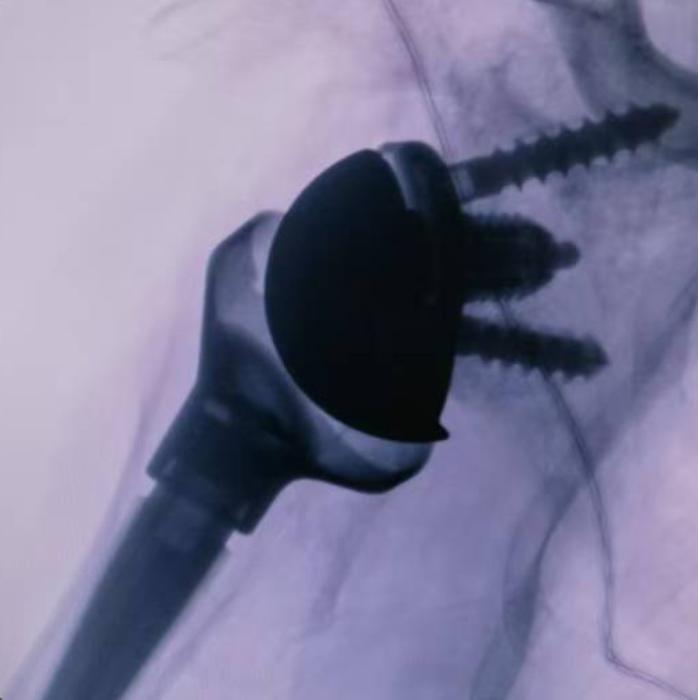

關(guān)節(jié)與運(yùn)動(dòng)醫(yī)學(xué)科陶崎峰主任醫(yī)師組織多學(xué)科討論,建議患者接受右反式人工肩關(guān)節(jié)置換術(shù)。手術(shù)由王洋主刀、劉浩、李勝發(fā)醫(yī)生聯(lián)合完成,過程順利,假體位置良好,術(shù)后疼痛明顯減輕,肩關(guān)節(jié)活動(dòng)度逐步恢復(fù)。此次手術(shù)的成功再次體現(xiàn)了醫(yī)院在復(fù)雜肩關(guān)節(jié)疾病治療及人工肩關(guān)節(jié)置換領(lǐng)域的專業(yè)實(shí)力。(吳平華 李勝發(fā) 劉浩 供稿)